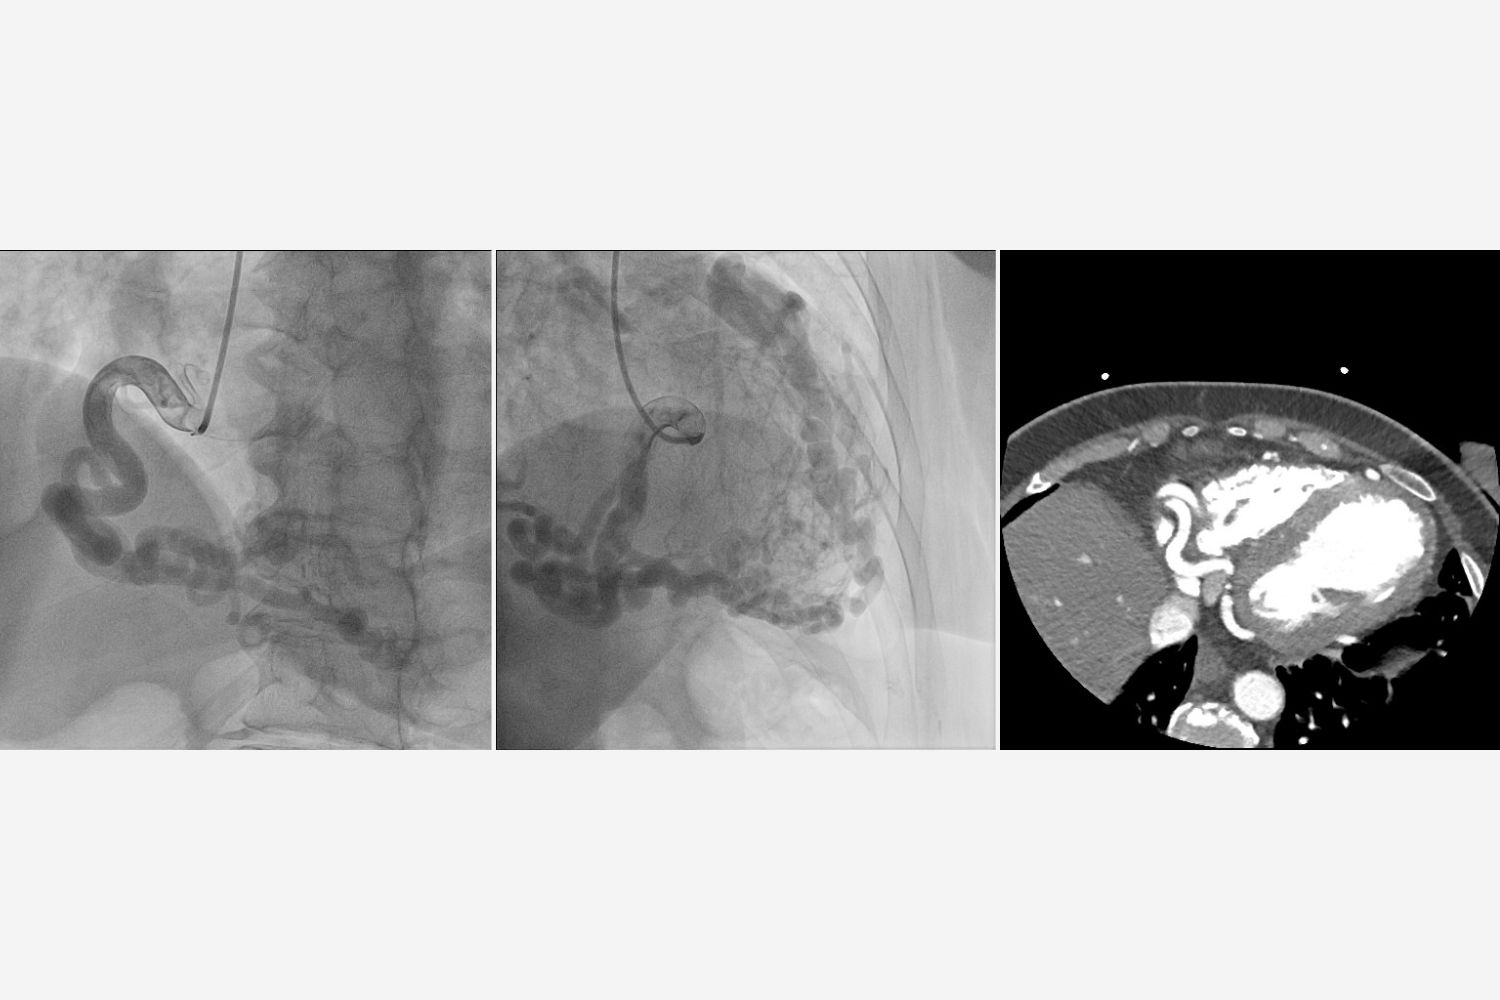

Image of the Week - 31 July 2024